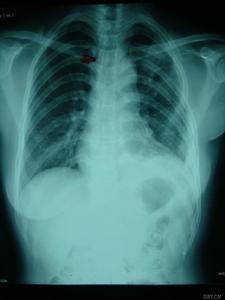

中心性軟骨肉瘤中心性軟骨肉瘤可表現為邊界模糊的溶骨,有或無皮質骨中斷,由於軟骨傾向於鈣化和骨化,腫瘤內可出現不透X線區,鈣化經常發生在軟骨小葉的周圍,無一定結構,其特徵為不規則的霧狀顆粒、結節或不透X線的環。

由於瘤壁骨嵴,腫瘤可產生泡狀或麵包屑樣外觀。如鈣化緻密,腫瘤可呈不透X線的金屬樣。如腫瘤浸潤到松質骨的髓腔而未破壞骨小梁時,鈣沉積和反應性骨增生可呈不透X線均勻一致的海綿骨樣。如腫瘤浸潤松質骨未破壞骨小梁且無鈣化時,骨內的腫瘤部分可不顯影,在這種情況下,如果不藉助骨掃描、CT和MRI,中心性軟骨肉瘤的診斷困難且晚。分化良好的中心性軟骨肉瘤鈣化多,而Ⅲ級中心性軟骨肉瘤及反分化中心性軟骨肉瘤鈣化少且粘液區多。皮質骨可以很薄,內部呈扇貝狀,在一些區域可有中斷。有時由於腫瘤膨脹緩慢,皮質骨發生增生,可顯得增厚。這種增厚的皮質骨表現相當典型,表明其已被腫瘤所浸潤。

中心性軟骨肉瘤傾向於向阻力較小的地方擴張,如骨幹的髓腔。在幾乎一半的病例中,放射影像顯示腫瘤侵犯整個長骨的1/3、1/2或更多,但在腫瘤早期,影像上可能無顯示。這個特點很重要,否則手術方案可能不恰當,切除緣可能不夠,於骨幹切除或截肢術後殘肢處腫瘤可復發,為避免發生,須在術前通過骨掃描、CT和MRI來確定腫瘤在髓腔內的範圍。

在侵襲性較強的病例中,中心性軟骨肉瘤早期即可有廣泛的皮質中斷,較大的軟組織腫塊,侵入軟組織中的瘤塊鈣化不明顯。受浸潤被頂起的骨膜可以反應性地產生薄的、稍不透X線的帶,垂直於皮質,但從不見在骨肉瘤中典型的“牙刷”影像以及Codman三角。